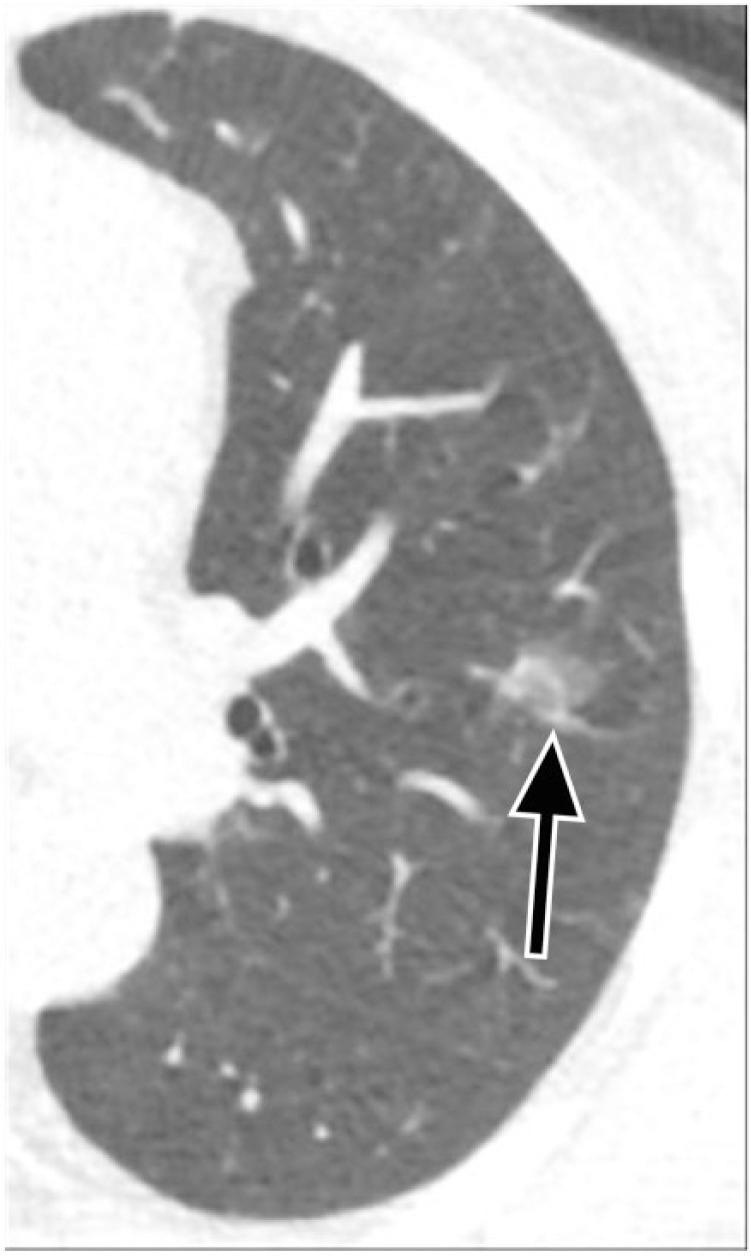

Pulmonary nodules, both solid and subsolid, are common incidental findings on computed tomography (CT) studies. Subsolid nodules (SSNs) may be further classified as either pure ground-glass nodules or part-solid nodules. The differential diagnosis for an SSN is broad, including infection, organizing pneumonia, inflammation, hemorrhage, focal fibrosis, and neoplasm. Adenocarcinomas of the lung are currently the most common type of lung cancer, representing 30-35% of all primary lung tumors, and the subtype of bronchioloalveolar cell carcinoma (BAC) commonly presents as an SSN. In 2011, a new classification system for lung adenocarcinomas was proposed by the International Association for the Study of Lung Cancer, the American Thoracic Society, and the European Respiratory Society. An important feature of the new system is the relinquishment of the term BAC in favor of more specific histologic subtypes. It has been reported that these subtypes are associated with characteristic CT findings. This article reviews the new classification system of lung adenocarcinomas, discusses and illustrates the associated CT findings, and outlines the current recommendations for further diagnosis, treatment, and follow-up of SSNs based on computed tomography findings.

肺部结节,无论是实性还是亚实性,都是计算机断层扫描(CT)研究中的常见偶然发现。亚实性结节(SSN)可进一步分为纯磨玻璃结节或部分实性结节。SSN 的鉴别诊断范围很广,包括感染、机化性肺炎、炎症、出血、局灶性纤维化和肿瘤。肺腺癌是目前最常见的肺癌类型,占所有原发性肺肿瘤的 30-35%,而细支气管肺泡细胞癌(BAC)亚型通常表现为 SSN。2011 年,国际肺癌研究协会、美国胸科学会和欧洲呼吸学会提出了一种新的肺腺癌分类系统。该系统的一个重要特点是放弃 BAC 一词,转而采用更具特异性的组织学亚型。据报道,这些亚型与特征性 CT 表现有关。本文回顾了肺腺癌的新分类系统,讨论并说明了相关的 CT 发现,并概述了基于 CT 发现对 SSN 进行进一步诊断、治疗和随访的当前建议。